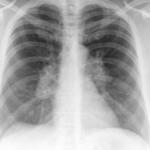

Signs

Album: Signs

Date: 04/28/2014

Size: 29 items

Views: 65423